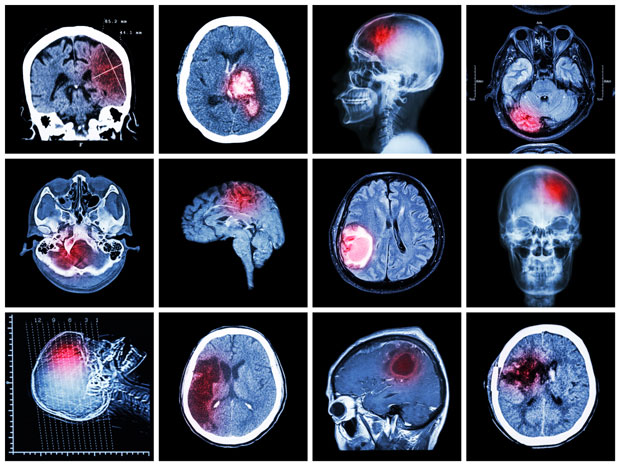

Američki neurolog Džejms Felon decenijama istražuje mozak najsurovijih psihopata i ubica uz pomoć magnetne rezonantne tomografije

Prema Felonovim rečima, za razliku od zdravih ljudi, kod psihopata je manje aktivan orbitofrontalni korteks — deo u sivoj masi direktno iznad očnog svoda koje je odgovorno za sposobnost vođenja društvenog života, etiku, moral, donošenje odluka, kontrolu nad impulsivnošću i agresivnošću.

Naučnici pokušavaju da utvrde kako se njihov mozak razlikuje od mozga normalne osobe i šta pretvara čoveka u serijskog ubicu.

Ranija istraživanja su pokazala da psihopate loše reaguju na fotografije koje obično izazivaju snažna osećanja. Čak je nastala hipoteza da kod njih nije razvijena amigdala — područje u mozgu u kome se obrađuju informacije o emocijama. Tu pretpostavku je 2001. godine potvrdio profesor sa Univerziteta u Nju Meksiku Kent Kilj pomoću MRT.

On je zajedno sa kolegama proučavao snimke magnetne rezonance 903 psihopate iz zatvora. U članku, koji je objavljen u martu ove godine, navodi se da su naučnici kod njih utvrdili smanjenu aktivnost delova mozga koji su odgovorni za emocije, kao i smanjene neuronske veze između delova koji kontrolišu osećanja poput empatije, krivice, straha i zabrinutosti.

Veruje se da je mozak serijskih ubica podložan organskim promenama. Na primer, istraživači sa Univerziteta iz Kalifornije uporedili su manijake sa epileptičarima, kod kojih povećanje neuronske aktivnosti mozga uzrokuje epileptični napad, a kod psihopata — ubistvo.

Poznato je da su kriminalci sposobni da prevare poligraf, suzbijanjem spoljnih znakova uzbuđenja, kao što je puls i cirkulacija. Ali teško da su u stanju da kontrolišu mozak, smatra Časi, i zbog toga skeniranje može da otkrije „neuronski potpis“ serijskog ubice, odnosno istovremeno aktiviranje dela mozga sa autobiografskim pamćenjem, koje reguliše seksualno zadovoljstvo, agresiju i emocionalnu kontrolu.